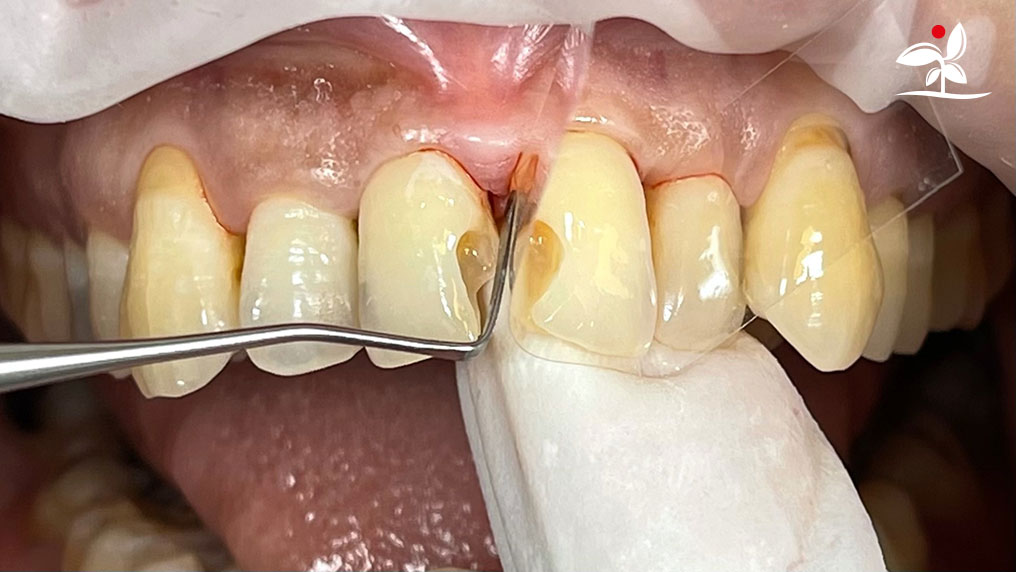

Restoration of Class IV Lesions using Naturomimetic Layering Technique (NLT) and Bioactive Restorative Materials

Dr Aung Pyae Phyo, Myanmar

include the methods of treatment that are simple, fast, predictable and healthy. In aesthetic restoration, the tooth color restorative materials placement technique is one of the most challenging, confusing and frustrating areas to learn owing to the multiple techniques that have been proposed by many clinicians and replicating such techniques in practice is not always as easy as they are marketed in dentistry. Natural teeth are complex in structure and hard to simulate due distribution of colors through enamel and dentin [2]. Aesthetic restoration strategies should follow proper understanding of defects, right selection of restorative materials along with their proper application, finishing, texturing and polishing [2].